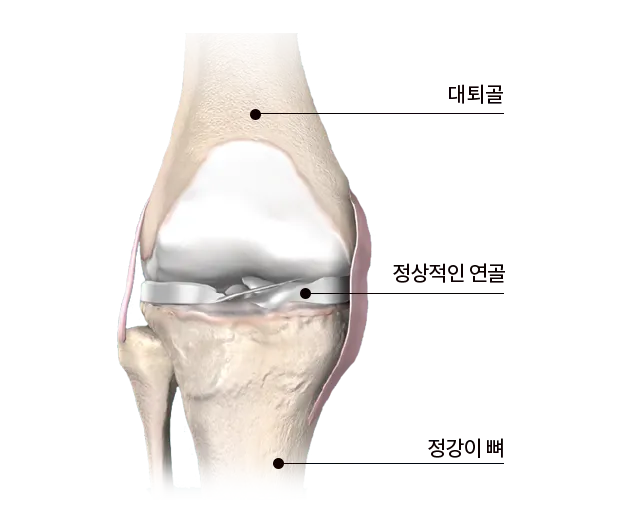

두 번째는 연골 손상

무릎 관절 사이에서 뼈와 뼈의 마찰을 줄여주는 부드러운 조직인 연골이 관련되어 있습니다. 나이 증가, 과체중, 관절염 등으로 인해 연골이 닳거나 소실되면, 뼈 사이의 직접적인 마찰로 인해 통증이 발생할 수 있으며, 이로 인해 움직임의 제한, 삐걱거리는 소리, 염증과 같은 증상이 나타날 수 있습니다.

이 상태의 치료는 체중 감량, 적절한 운동, 보조기 사용과 같은 자가 관리와 필요에 따라 진통제, 항염제, 보호주사, 관절경 수술 등의 의학적 치료를 포함할 수 있습니다.